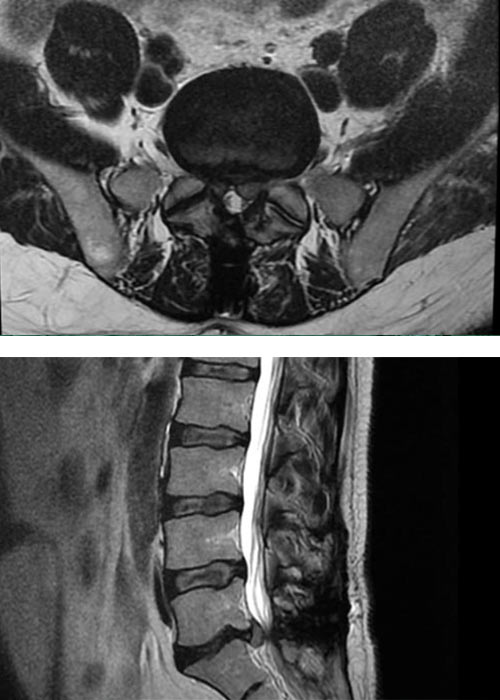

operacion-recidiva-hernia-discal-en-madrid

Operación

Con nuestra técnica ultra mínimanente invasiva, mediante incisión de 3mm le solucionamos el problema y el paciente no ha requerido fijación

postoperatorio-recidiva-hernia-discal-en-madrid

Postoperatorio

El paciente no ha requerido fijación, ni ha tenido que sufrir ningún postoperatorio complicado.

De forma inmediata el paciente ha notado una gran mejoría. Él mismo alegaba no sentir ningún dolor por lo que se ha concluido la operación sin ninguna complicación y con una gran satisfacción por parte del paciente..